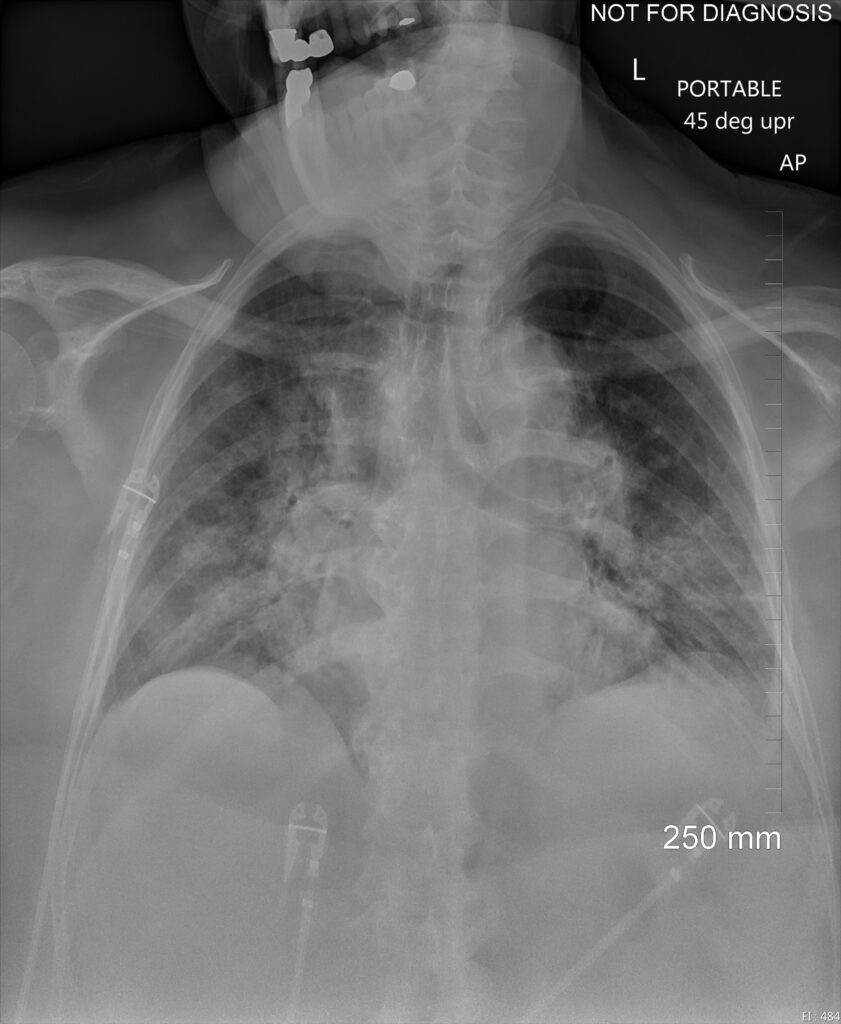

Follow-up of established disease: On CXR and CT, GGOs and focal area of consolidation often progress and may evolve into a bilateral acute respiratory distress syndrome-like pattern when cytokine storm develops. Less common CT findings include dilated peripheral pulmonary vessels, adenopathy, rounded infiltrates, and signs of bronchial inflammation. Hospital-acquired bacterial pneumonia may complicate COVID-19 and vice versa. Preexisting lung disease (e.g., chronic obstructive pulmonary disease, interstitial lung disease, etc.) further complicate interpretation. Clearing usually starts after 2 weeks.

COVID-19 may cause hypercoagulability, leading to an increased incidence of both emboli and in situ thrombi and deep vein thrombosis.

Pleural effusions may appear late, and barotrauma causing pneumothorax appears to be more common than in other viral pneumonias.